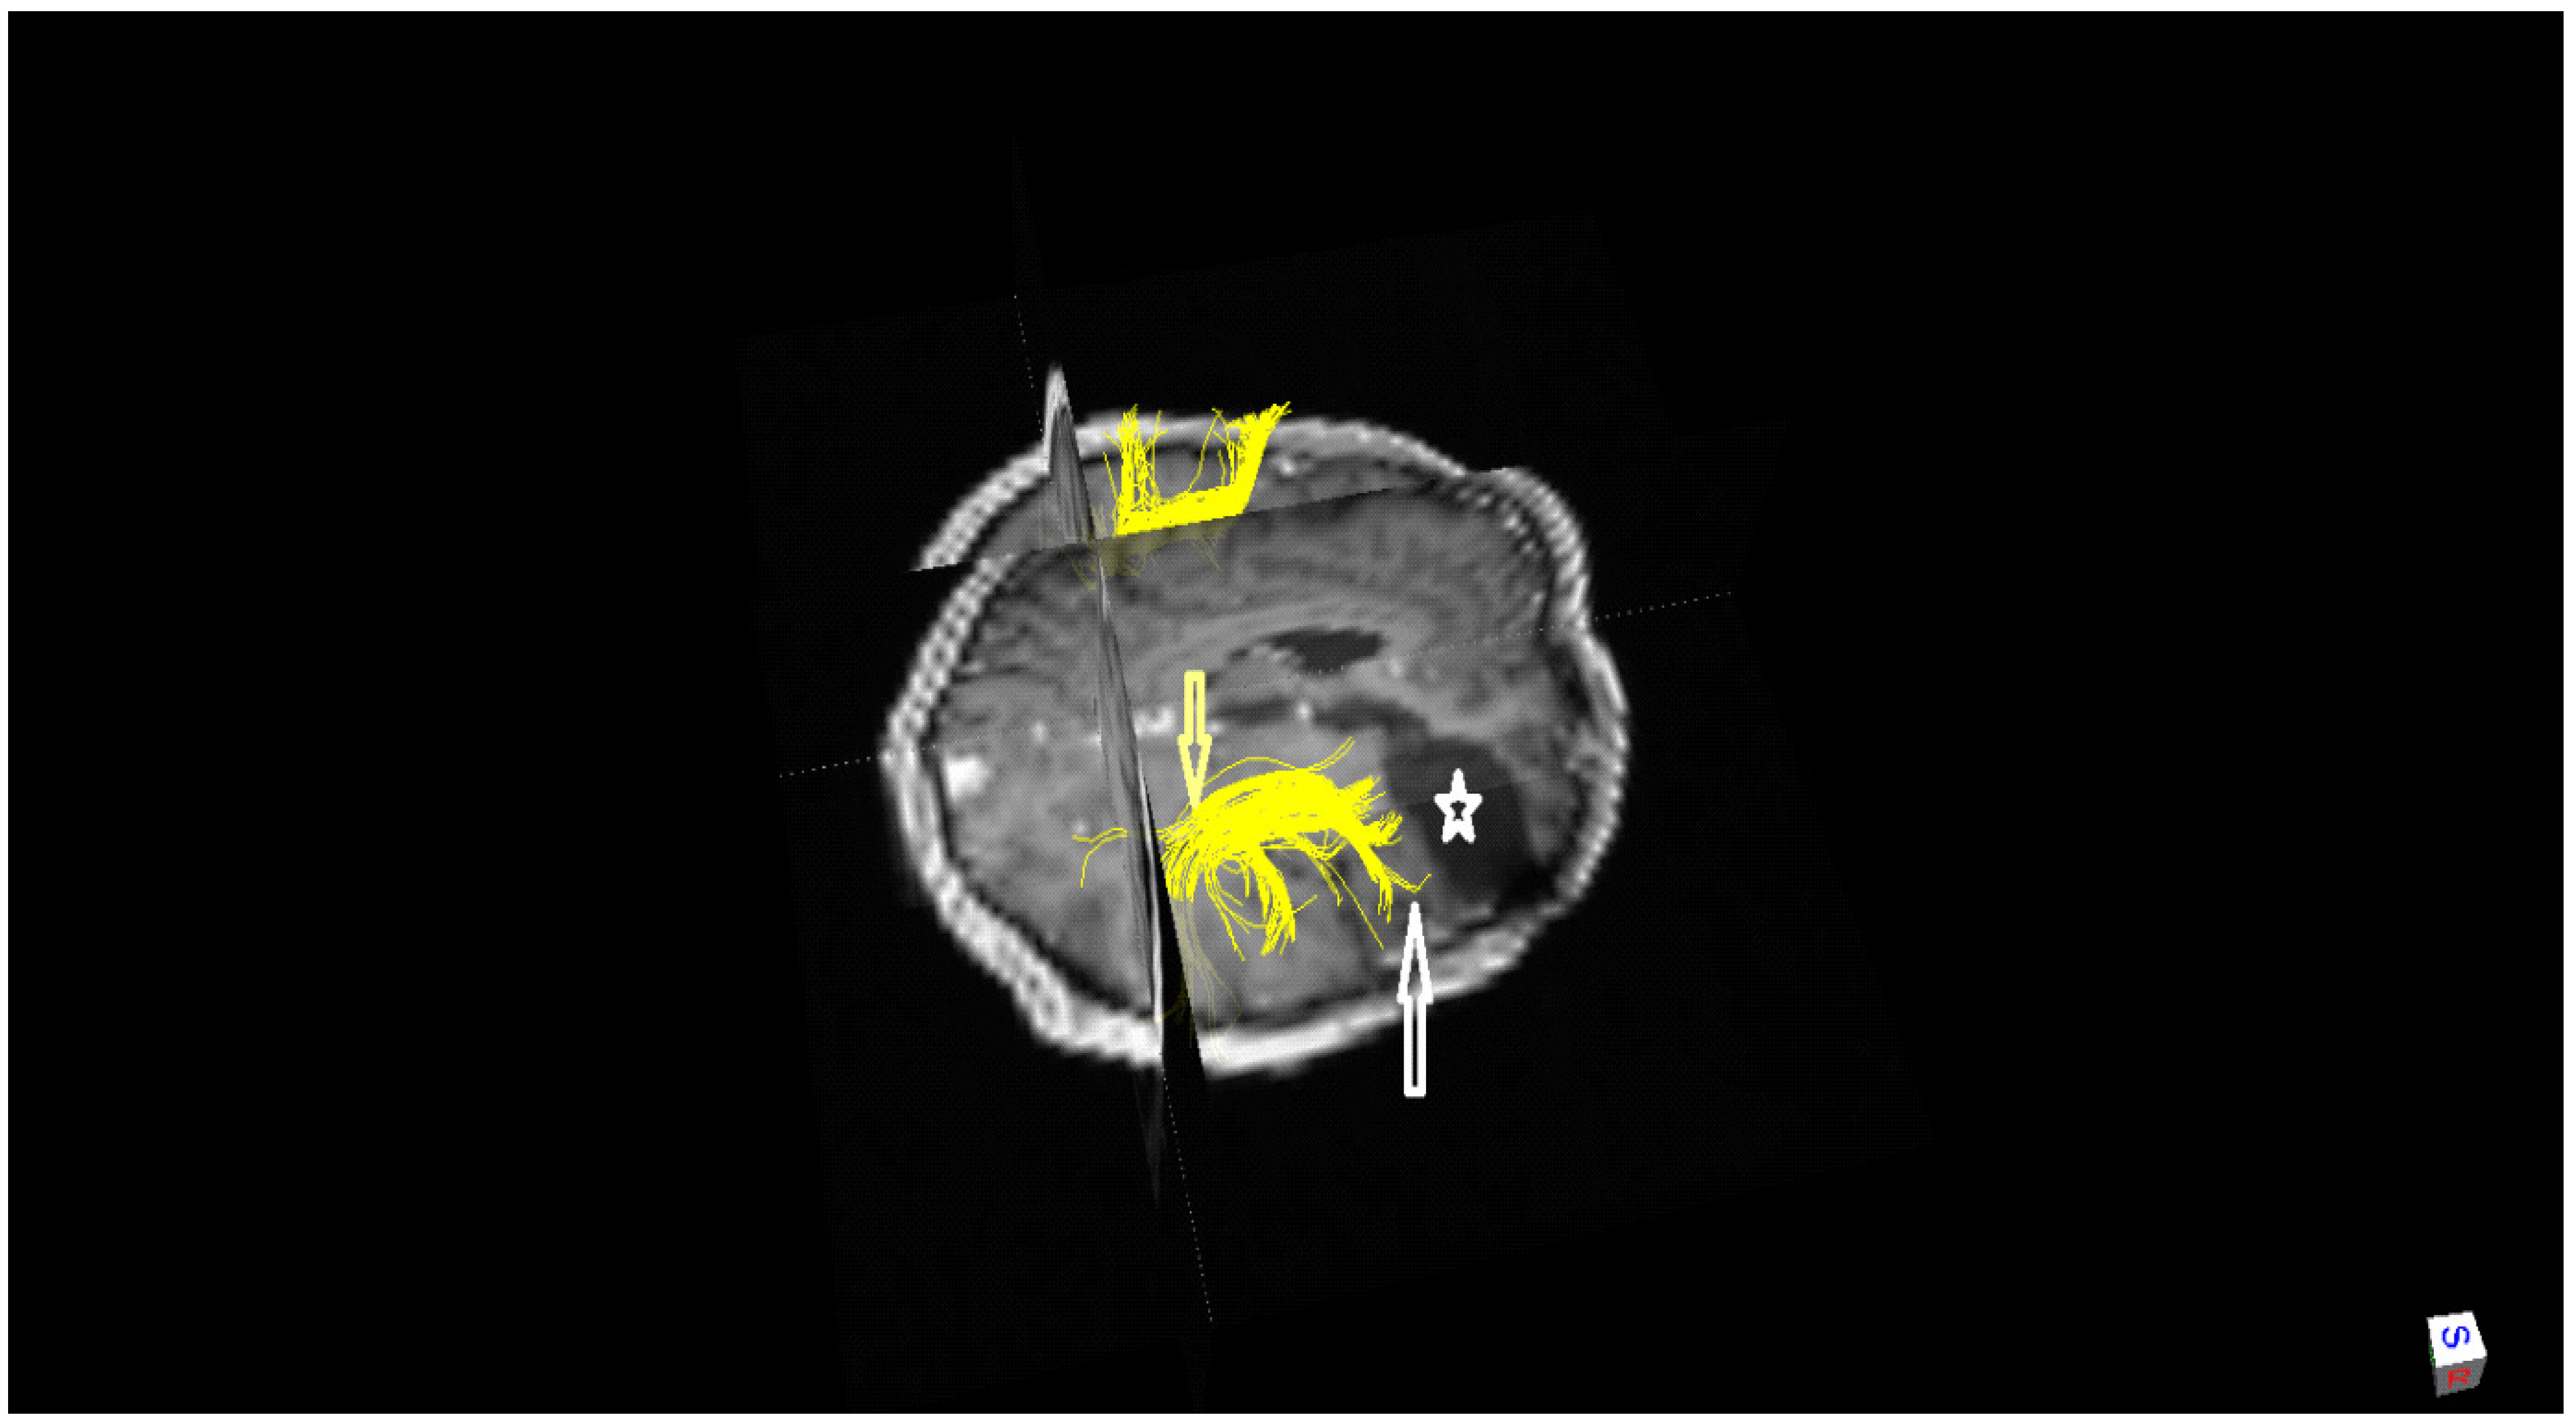

2.1. History, Neuro-Imaging and Surgical Treatment